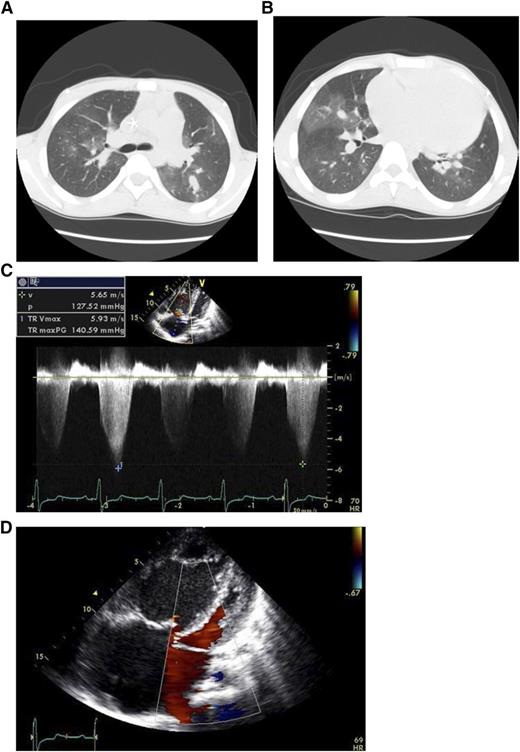

Patient case: An 18-year-old male patient with homozygous hemoglobin SS disease was evaluated for progressive dyspnea and elevated tricuspid regurgitant jet velocity (TRV) on echocardiography. The patient’s case is described in detail in Lancet.1 He had been treated with regular transfusions since childhood for stroke, had rare episodes of vaso-occlusive pain episodes, and did not take narcotic pain medications. He presented with progressive severe dyspnea on exertion and lower extremity edema. His laboratory tests were notable for a total hemoglobin level of 11.8 g/dL and hemoglobin S levels <30% but with 18% reticulocytes and elevated markers of hemolysis, such as high plasma levels of lactate dehydrogenase, aspartate amino transferase, and indirect bilirubin. The computed tomography scan of his chest in Figure 1A-B shows a large pulmonary artery, which has a greater diameter than his aorta, and a mosaic perfusion pattern, typical for severe pulmonary arterial hypertension. His Doppler echocardiographic study (Figure 1C) showed an unusually high TRV of 5.93 m/s, consistent with a calculated pulmonary artery systolic pressure of >140 mm Hg (4 times the TRV squared = 4V2). Additional images in Figure 1D show a dilated right ventricle and right atrium with a compressed left ventricle. The patient’s right heart catheterization revealed a pulmonary artery systolic pressure of 147 mm Hg and diastolic pressure of 49 mm Hg; note that the normal values are ∼25/10 mm Hg.

Imaging from an 18-year-old male patient with homozygous hemoglobin SS disease. (A,B) CT scan demonstrating large pulmonary artery and mosaic perfusion pattern due to areas of higher radiodensity where the blood flow is high (more white), next to darker areas where the pulmonary arterioles are narrowed and blood flow is reduced. (C) Doppler echocardiographic study records a very high tricuspid regurgitant jet velocity (TRV) of 5.93 m/s, which estimates a pulmonary artery systolic pressure of greater than 140 mm Hg. (D) Four-chamber view of his heart shows shows a dilated right ventricle (RV) and right atrium (RA) with a compressed left ventricle (LV).